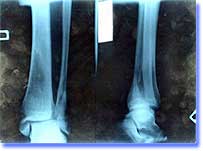

Алексей Коновалов КЛЮХ Киев получил тяжелейшую травму ноги.

В игре против Киевского Беркута после грубого силового приема Алексей влетел в борт и сломал обе лодыжки на правой ноге. Перелом оказался очень сложным со смещением пятки, на ногу поставили несколько пластин, с которыми Алексей будет ходить несколько лет.